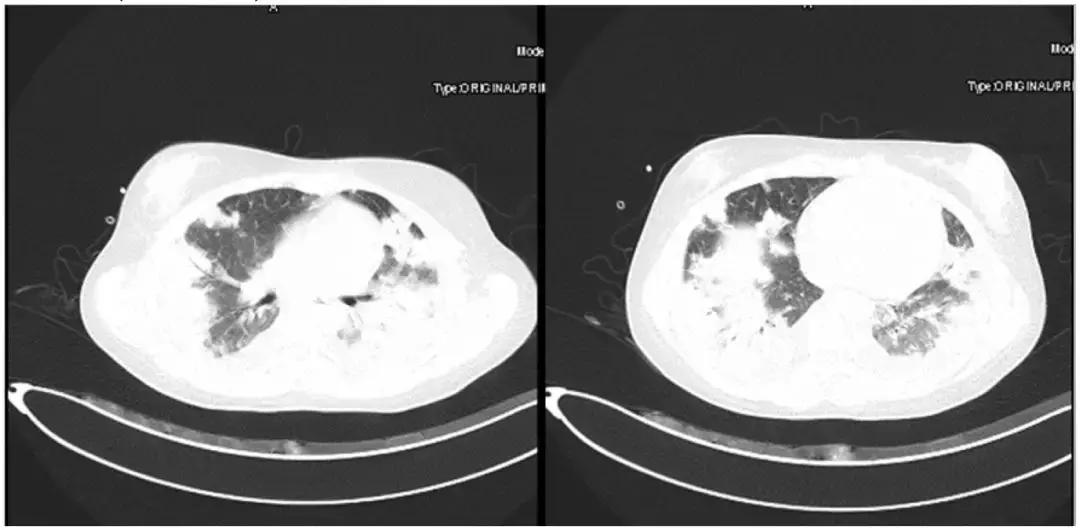

胸部CT(6月27日)提示双肺多发实变、斑片影、结节影。

*影像学显著进展

7月3日:

7月10日: